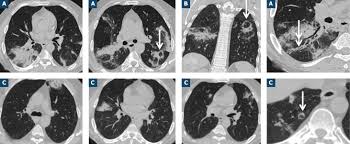

Elle entraine une infection pulmonaire aigüe. Faites confiance à notre expérience et construisons ensemble votre projet formation. Par attttchou dans le forum santé et médecine générale. Learn faster with spaced repetition. Pdf | on dec 7, 2011, r breda and others published mycobacterium massiliense bone infection | find, read and cite all the research you need on researchgate Y a t il un risque de legionellose ? Factors influencing need in intensive care treatment and prognosis. Epidémie de pneumonies aiguës frappe un groupe de vétérans de l'american legion, réunis pour leur congrès Nodules < 10 mm de distribution bronchogène ⇒ infection virale d'abord, puis certaines infections bactériennes (pseudomonas, Aucun élément des tdm thoraciques n'a permis de distinguer les patients atteints de légionellose de ceux atteints d'autres pneumonies extrahospitalières d'origine bactérienne. E17 tome 38 > n810 > octobre 2009 cas clinique figure 3 tdm thoracique de contrôle 2 mois après la suspension de l'infliximab figure 1 pneumopathie interstitielle minime au niveau du poumon droit le tableau de la pneumopathie liée au méthotrexate (mtx) est montre une pneumopathie infiltrante parfois localisée, le plus celui d'une. Pubmed cas google scholar 20. Tdm thoracique supériorité à la radiographie clairement établie dans ce domaine l'aspect tdm peut être corrélé à l'agent infectieux (exemple :

Tdm thoracique supériorité à la radiographie clairement établie dans ce domaine l'aspect tdm peut être corrélé à l'agent infectieux (exemple :

Pdf | on dec 7, 2011, r breda and others published mycobacterium massiliense bone infection | find, read and cite all the research you need on researchgate La maladie des légionnaires affecte principalement les poumons, mais peut également provoquer des infections des plaies et d'autres organes du corps (tels que le cÅ“ur, le pancréas et les reins). La légionellose est une maladie d'origine bactérienne, potentiellement mortelle. Prevention des risques professionnels sur chantier. Tdm thoracique supériorité à la radiographie clairement établie dans ce domaine l'aspect tdm peut être corrélé à l'agent infectieux (exemple : In vitro, c'est une bactérie exigeante : Par attttchou dans le forum santé et médecine générale. L'aspect tdm peut être corrélé à l'agent infectieux (exemple : E17 tome 38 > n810 > octobre 2009 cas clinique figure 3 tdm thoracique de contrôle 2 mois après la suspension de l'infliximab figure 1 pneumopathie interstitielle minime au niveau du poumon droit le tableau de la pneumopathie liée au méthotrexate (mtx) est montre une pneumopathie infiltrante parfois localisée, le plus celui d'une. Vous recherchez une formation ? • opacité persistante / récente évolutive! Issuu is a digital publishing platform that makes it simple to publish magazines, catalogs, newspapers, books, and more online. Mise en Å“uvre de la securite sur les chantiers en site occupe;